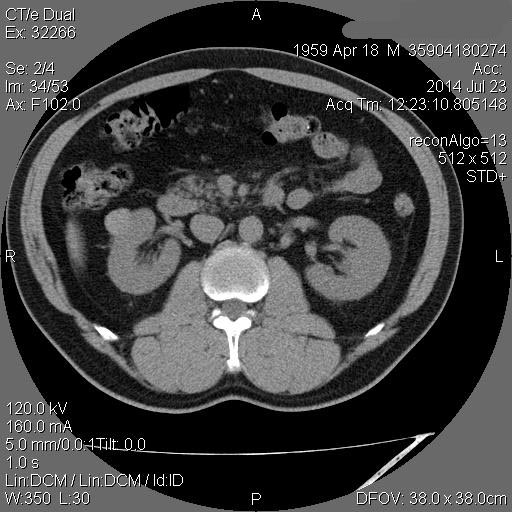

Образование в правой почке

Мужчина средних лет.Жалоб не предъявляет.

С его слов, 10 лет назад в правой почке находили кисту.

Рак - на первом месте. Показано КТ с контрастирванием.

гипоэхогенное образование в среднем сегменте, деформирующее контур почки...наверное рак

Ответ каунасских радиологов - киста почки.

В том то и дело. Но тем не менее - это киста, анамнез уже несколько лет.besliu писал(а):Что-то на узи на кисту не похоже...

Динамики нет, на последнем видео четко видна киста при включенной 2й гармонике